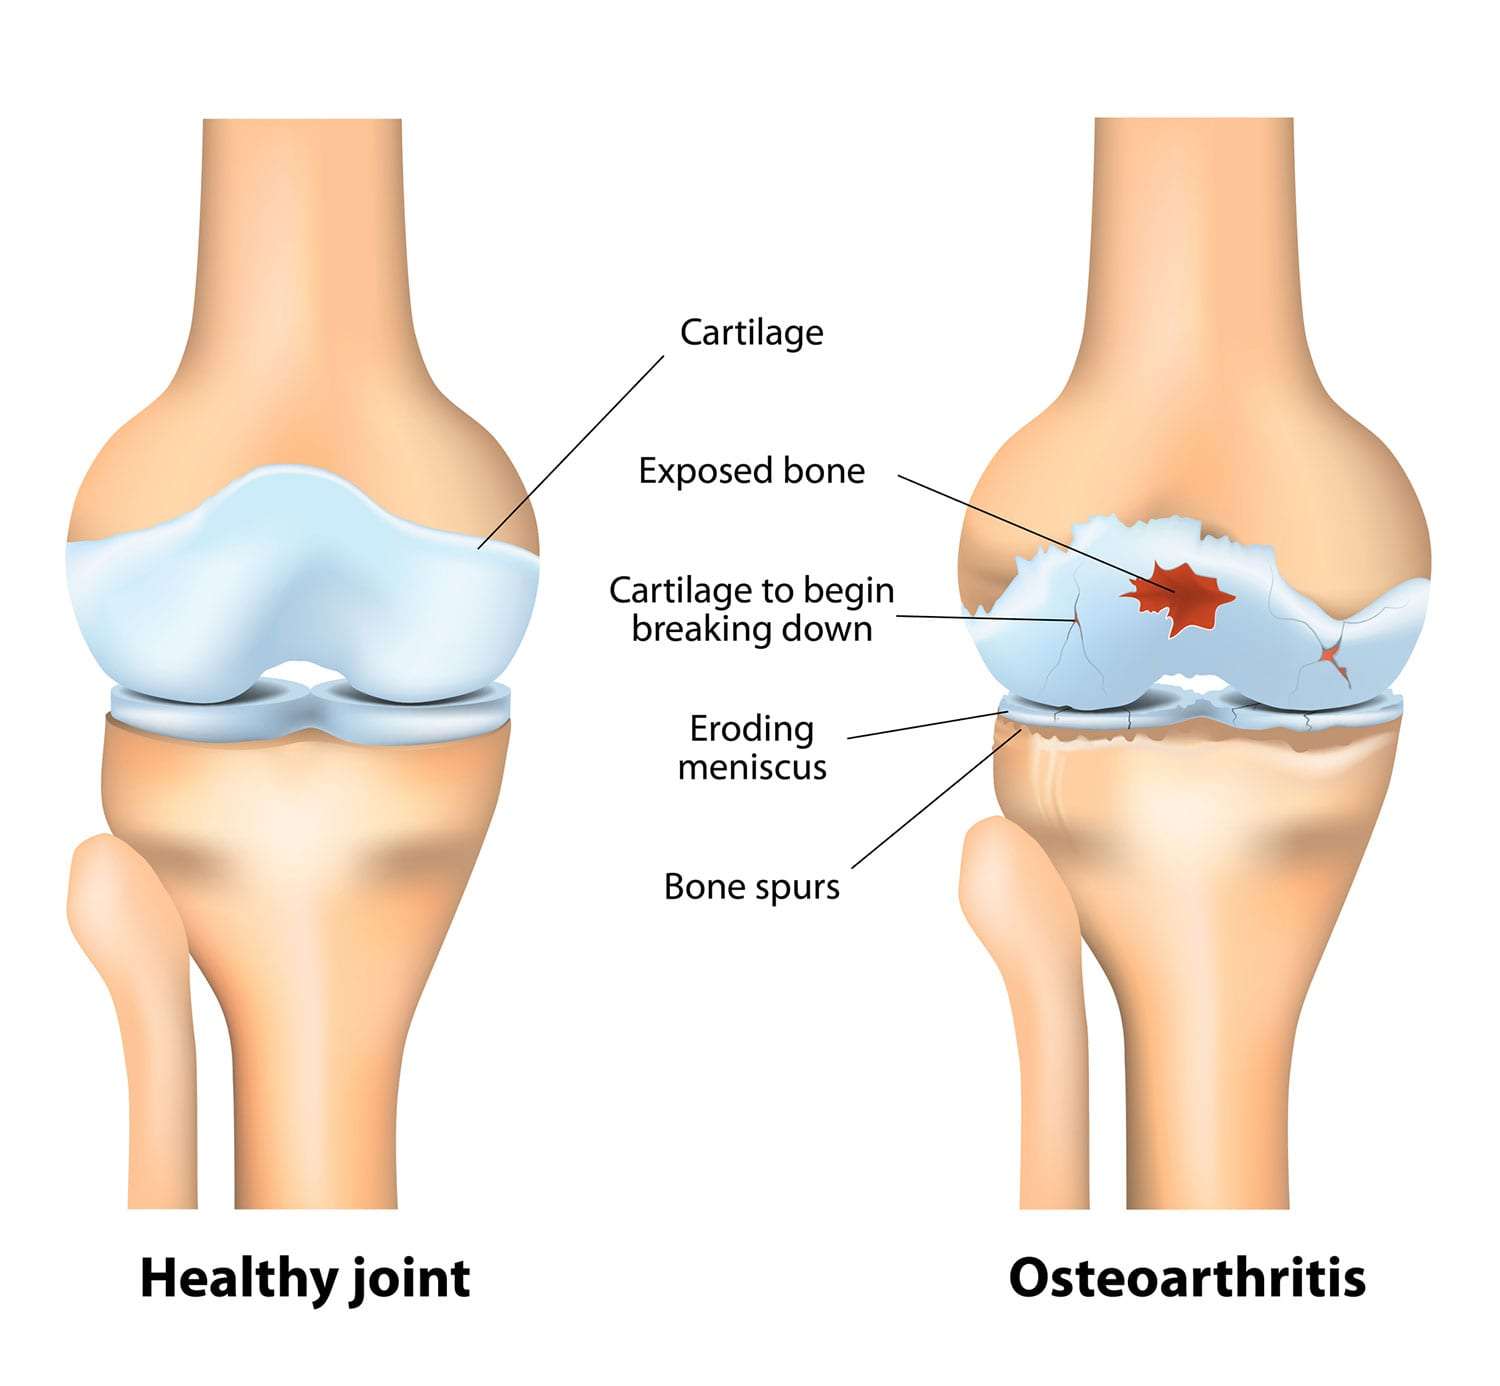

Why Women Face Higher Risk of Osteoarthritis?

Did you know that women are almost twice as likely as men to develop osteoarthritis? Joint pain in women is becoming more and more common,

When Does Arthritis of Joint Need Surgery?

Did you know? Arthritis is one of the most common causes of disability globally. And when it hits your knees, it doesn’t just hurt, it